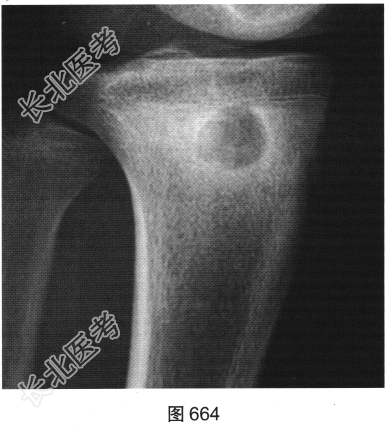

- 多项选择题3.[提示]患者行右小腿X线平片及CT、MRI检查,见图664~图666。该病最可能的诊断是( )

A、Brodie骨脓肿

- 多项选择题4.Brodie骨脓肿的诊断依据是( )

A、MRI囊内为液性信号并见环状等信号薄壁,周围见水肿区

B、CT示囊样骨质破坏,边缘有硬化

C、患者为青少年

D、X线见类圆形骨质破坏,边界清楚伴边缘骨质硬化

E、发热、患肢疼痛、肿胀等典型症状

F、起病较急